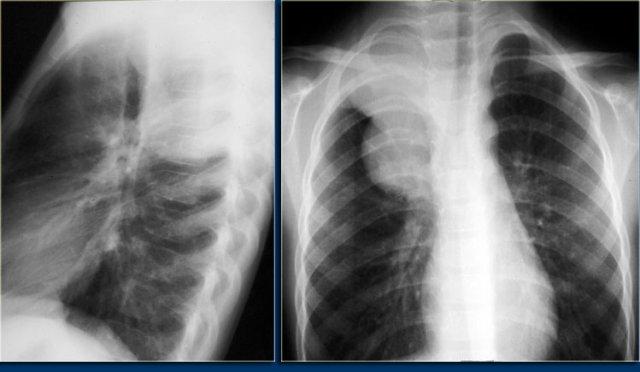

Nang thần kinh – ruột

Nang thần kinh chứa các thành phần thần kinh và tiêu hóa.

Chúng thường đi kèm với các dị tật đốt sống và vẹo cột sống. Nang không thông với dịch não tủy.

Nang có ranh giới rõ ràng, có giá trị tỷ trọng gần bằng nước trên CT và tín hiệu tương đương nước trên MRI, như được minh họa trong trường hợp bên trái.